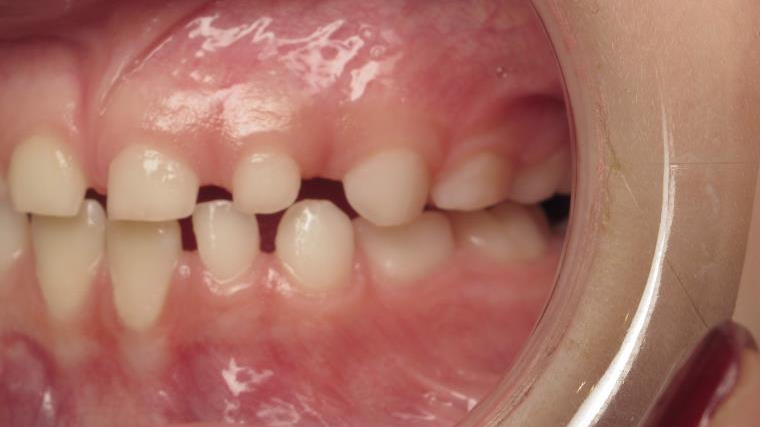

inversion postérieur coté droit et espace entre les dents du haut et du bas (diastèmes)

appareillage mobile pendant 35 mois

bilan début et en cours de traitement